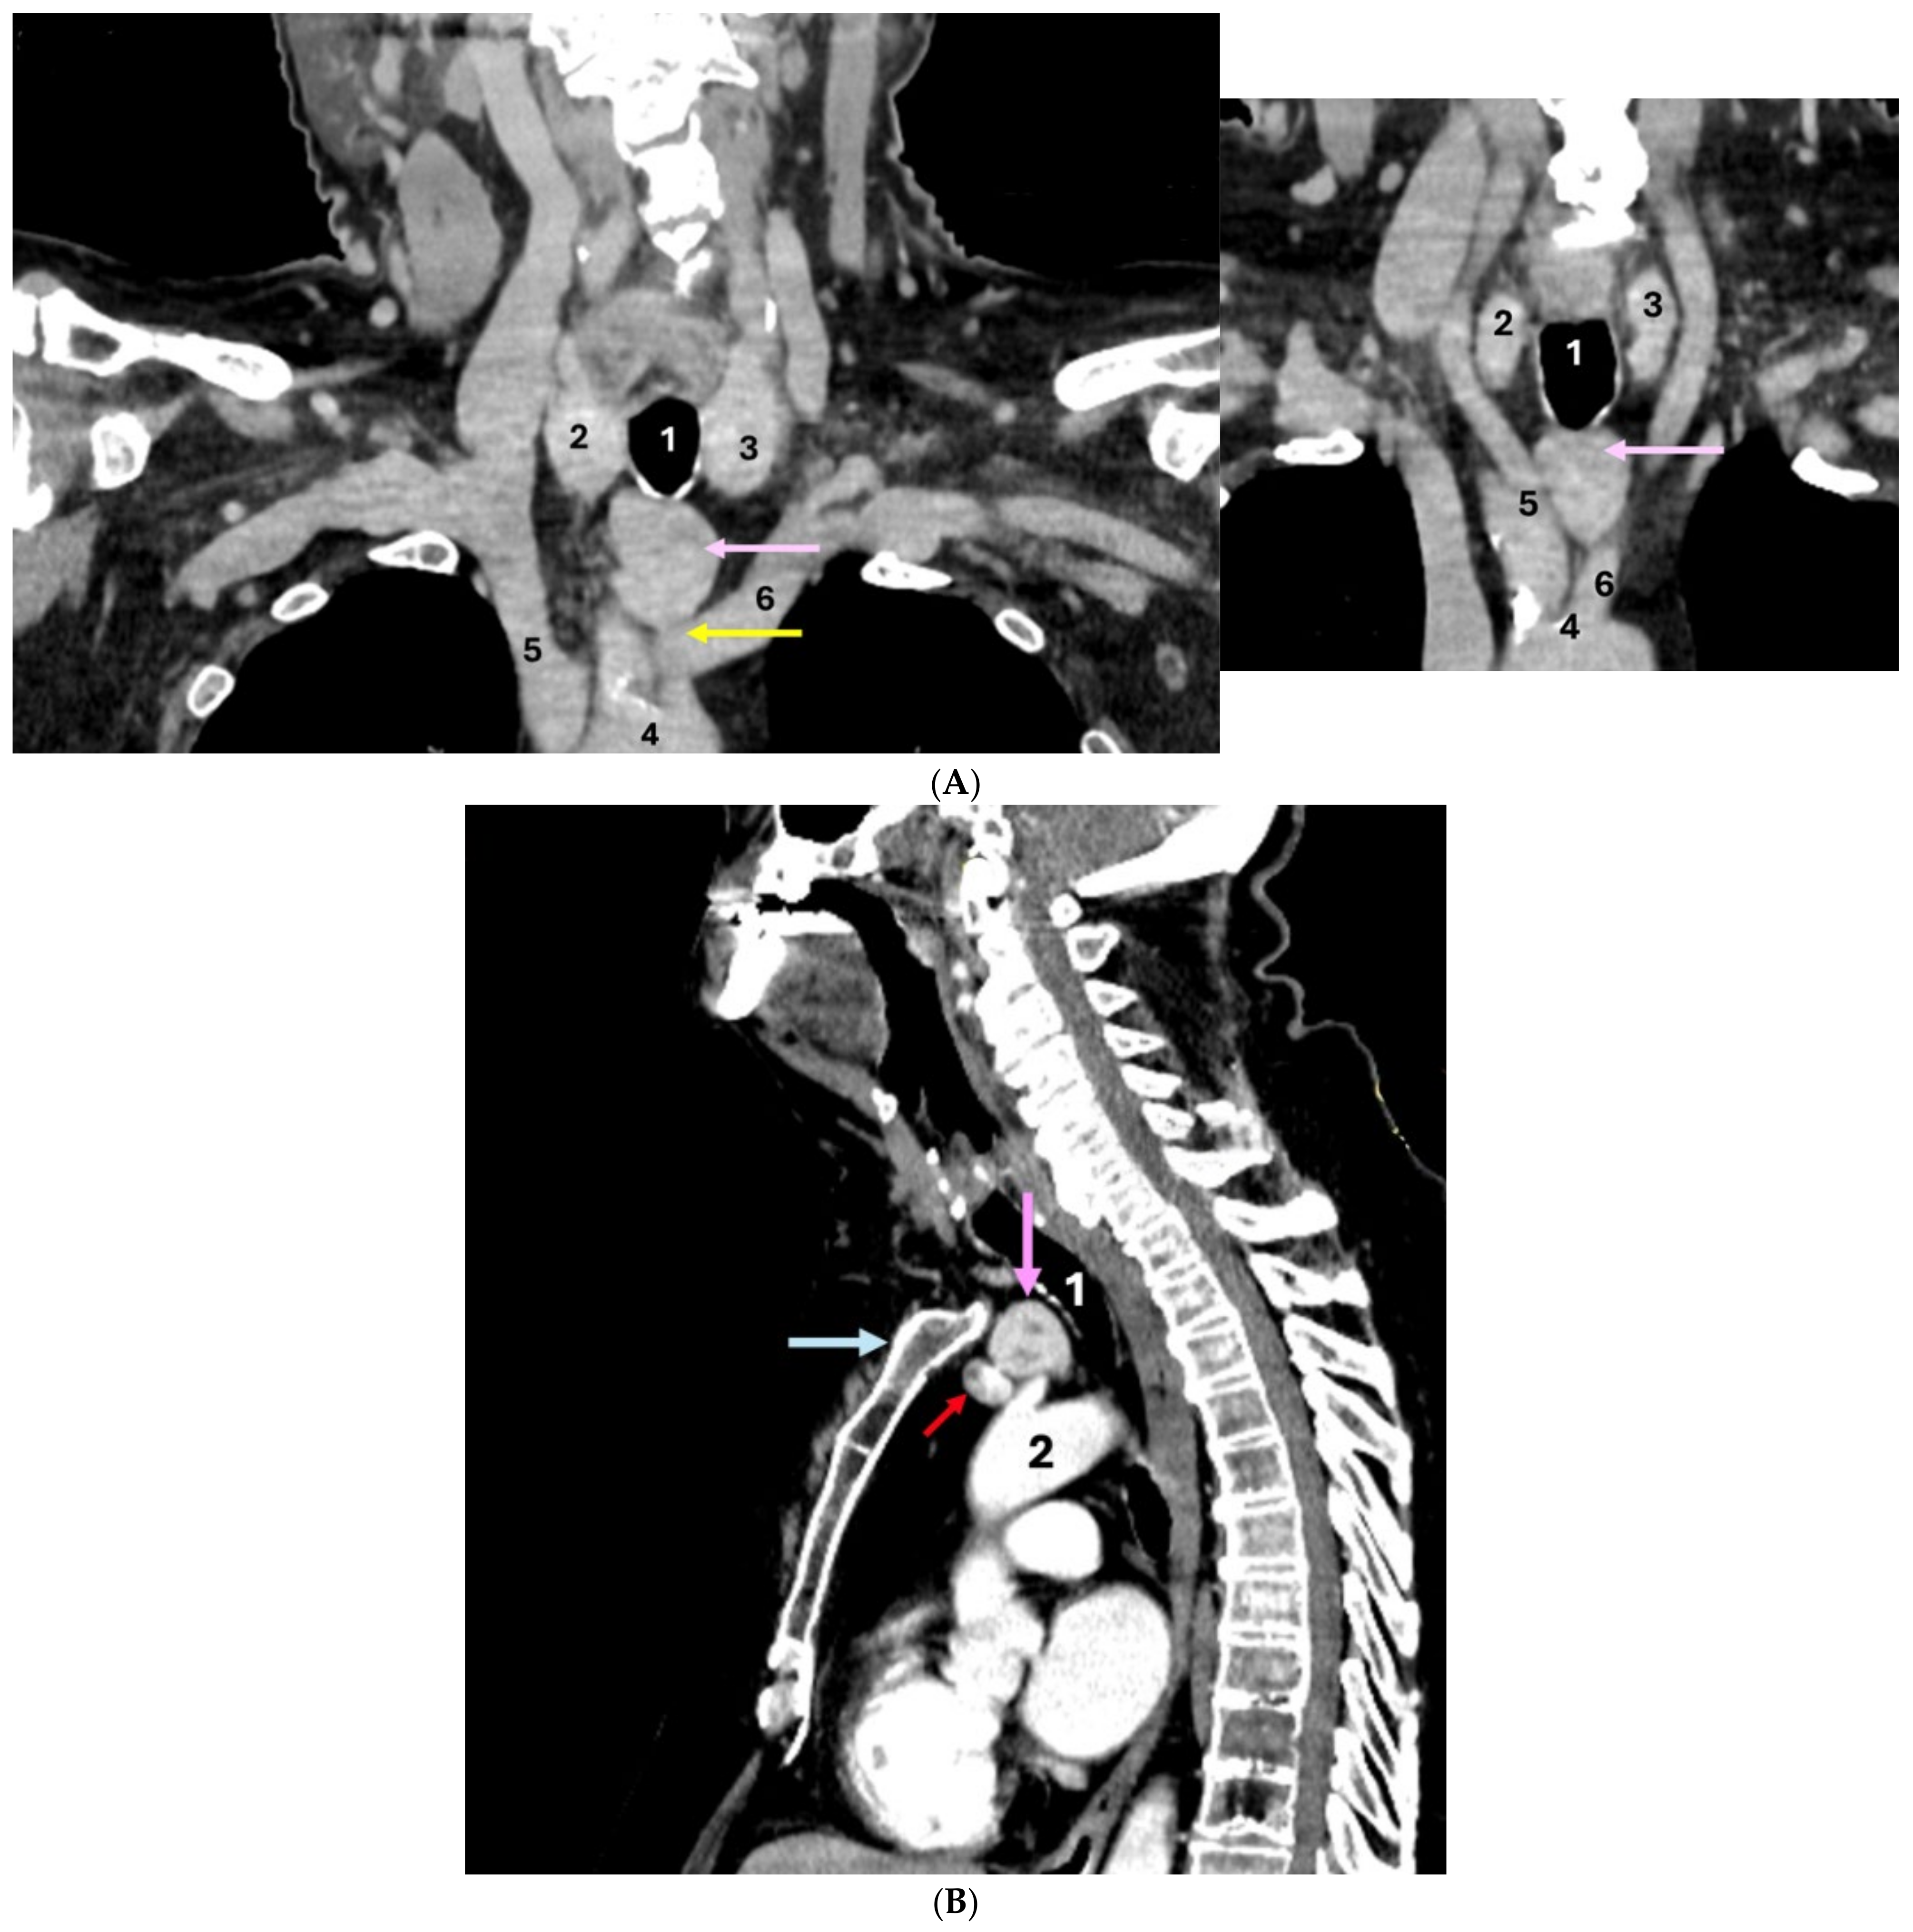

IV contrast CT scan showed a minimally asymmetric thyroid gland and a dense, intensely iodophilic mass (ETTM) with a transverse diameter of 2.66 cm, antero-posterior diameter of 2.33 cm, and cranio-caudal diameter of 3.17 cm, located in the upper mediastinum at the level of the jugular notch, in close contact with the mediastinal blood vessels and with an imprecise cleavage plane from them. ETTM showed independent blood supply: of the arterial type coming from the left common carotid artery, respectively, of venous type, originating from the left brachiocephalic venous trunk (Figure 6).

Figure 6.

Contrast-enhanced CT scan showed: (A) Coronal plane (two different sections): 1—trachea; 2—right thyroid lobe; 3—left thyroid lobe; 4—ascending aorta; 5—brachiocephalic trunk; 6—left common carotid artery; ectopic thyroid (pink arrow); arterial supply (yellow arrow) for the ectopic thyroid, originating from the left common carotid artery. (B) Sagittal plane: 1—trachea; 2—ascending aorta; venous supply (red arrow) for ectopic thyroid, originating from the left brachiocephalic venous trunk; ectopic thyroid (pink arrow); manubrium (blue arrow).